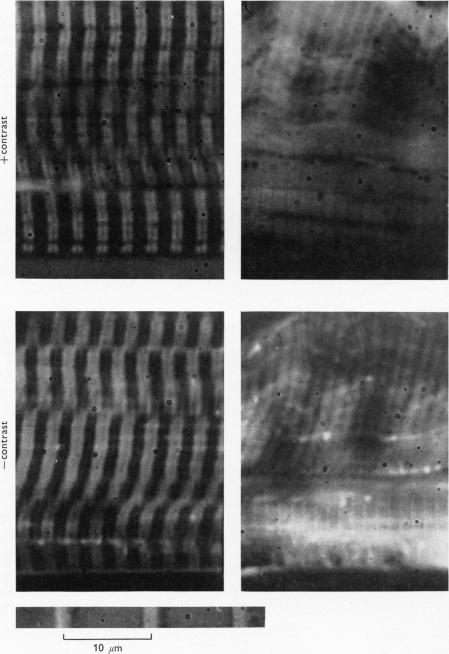

Muscular contraction.

J Physiol. 1974 Nov;243(1):1-43.